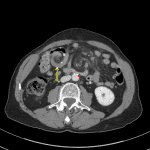

Indication: Concern for bowel obstruction (no surgical history available)

- Swirling of the small bowel mesentery with occlusion of the SMV

- Surgical changes of cholecystectomy and hepaticojejunostomy with proximal side-to-side anastomosis and swirling of the efferent bowel loop and associated mesentery just proximal to the distal anastomosis

- Edema throughout the central small bowel mesentery with scattered mildly enlarged mesenteric lymph nodes

- No pronounced segmental bowel wall thickening, pneumatosis, or portal venous gas

- No bowel obstruction

Midgut volvulus

Findings concerning for midgut volvulus with resultant occlusion of the SMV and extensive mesenteric edema. No convincing pneumatosis or evidence of perforation. Recommend surgical consultation.

Surgical changes of cholecystectomy and hepaticojejunostomy with swirling of the efferent bowel loop and associated mesentery just proximal to the distal anastomosis. This finding raises the possibility of an internal hernia, though this patient’s expected postoperative anatomy is unclear in the absence of prior comparison studies. No evidence of bowel obstruction.